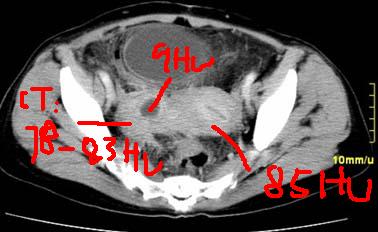

患者,52,右下腹疼痛一月,当时有发热,抗炎治疗20余天,至今仍疼痛,且有低热。

临床特点:

右下腹疼痛一月,当时有发热,抗炎治疗20余天,至今仍疼痛,且有低热,具有典型炎症的临床表现。

ct表现:

右侧附件见一肿块,边缘与周围组织分界不清,增强扫描见肿块明显强化,越到后期强化越明显,中央见坏死,内壁光整,与临近子宫壁、直肠及膀胱后壁均见炎症波及。这种厚壁肿块、内缘光整外缘模糊、增强扫描强化越后越强是附件脓肿典型的ct表现。

诊断:

右侧卵巢输卵管慢性脓肿,炎症波及临近子宫、直肠及膀胱形成粘连。